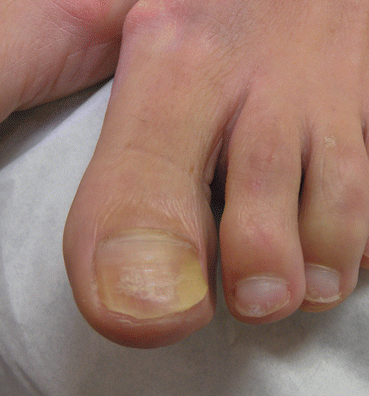

However, lichen planus can also affect the nail bed causing subungual hyperkeratosis and onycholysis. In the toenails it often causes yellow discoloration and thickening (yellow nail syndrome-like presentations) (Fig. 14.3). In general, patients also present signs of nail matrix involvement that suggest correct diagnosis.

Fig. 14.3

Nail bed lichen planus. Nails are thickened and yellow in color; note onychorrhexis that suggests correct diagnosis